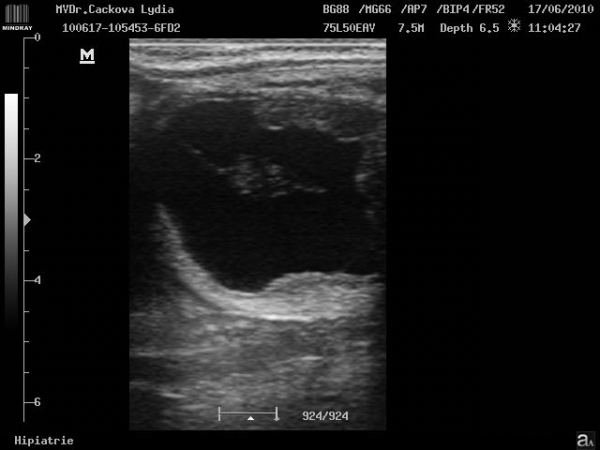

ultrasonografické vyšetření klisny

Preovulační folikul